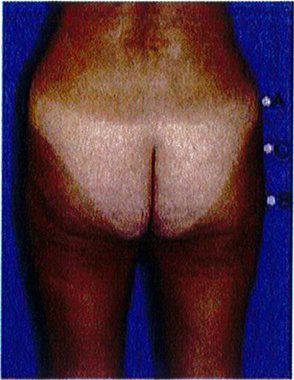

Khung vuông là phổ biến nhất, gặp ở khoảng 40% số bệnh nhân. Vị trí A và B tương tự nhau, đặc trưng cho phần mông hình vuông để khi các điểm này nối với nhau sẽ được một hình vuông (Hình 7 và 8). Điểm C có thể có các mức độ lõm (thiếu mô mỡ) khác nhau. Đây là dạng khung dễ chỉnh hình nhất trong cả 4 kiểu khung vì bất kỳ sự thay đối nào ở 1 trong 3 điểm A,B,C đều có thể biến khung này thành dạng khung khác.

Short Square Buttock – Round implant is best

Short gluteus: height and width is the same (1:1 ratio)

Tall Square Buttock – Best to use an anatomic implant

Tall gluteus: the muscle is taller than it is wide (2:1 ratio)

ình. 8. Hình minh họa khung vuông, cao. Cơ mông lớn có tỉ lệ cao/rộng = ..

Dạng còn lại là dạng trung gian, nằm giữa dạng khung cao và khung thấp vừa mới đề cập ở trên. Cơ mông lớn có chiều cao/rộng = 1:1 hoặc 2:1. Mông dạng vuông thường được cải thiện tương đối nhiều khi hút mỡ điểm A và B. Điểm C có thể cần ghép mỡ, tùy thuộc vào mức độ lõm tại điểm này (Hình 9).

Hình dạng này độc đáo ở chỗ chúng có thể cao, trung bình hoặc ngắn (Hình 7 và 8). Để hiểu rõ khái niệm này, cần phải nhớ rằng khung bao gồm da, mỡ và xương. Khung xương chỉ hữu ích để xác định đây là khung cao, trung bình hay ngắn. Giới hạn trên của khung xương là đường viền trên của mào chậu. Nên tùy thuộc độ cao của chúng mà cơ mông lớn sẽ bám vào khung xương tại các vị trí khác nhau. Cụ thể, biến thể đầu tiên gắn đường viền trên cơ mông lớn dọc Theo đường viền trên của toàn bộ mào chậu, chúng để lại rất ít khoảng trống giữa bờ trên của cơ và mào chậu. Loại này hình thành khung chậu ngắn, tỉ lệ cao/rộng của khối cơ là 1:1. Dạng biến thể thứ hai, cơ bám thấp hơn trên khung chậu, sao cho mép trên của cơ cách mào chậu khoảng ½ chiều dài cơ. Loại này được gọi là khung chậu cao, cơ thường có tỉ lệ cao/rộng là 2:1 (Hình 8)